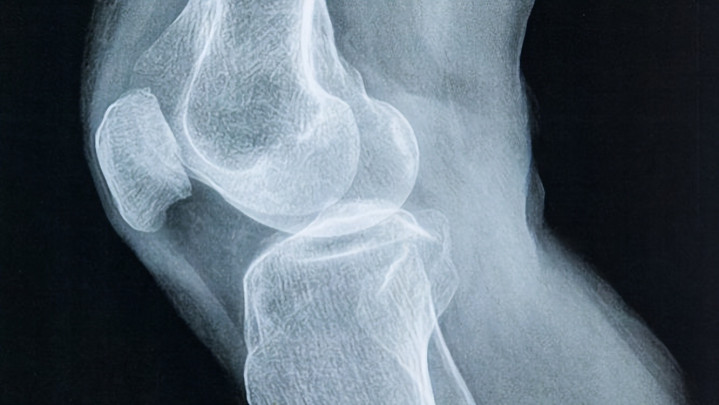

不少东谈主看到这种体检猖狂时齐会有点讶异。年事增长后,骨头相同会厚重变得脆弱,这是医学上非相同见的表象。骨密度下落到一定进程,就会被会诊为骨质疏松。许多东谈主以为这是不成幸免的老年问题,其实骨骼健康与活命神气相关很大。

骨头并不是静止不变的结构,它一直在进行代谢更新。骨造成和骨罗致保握均衡时,骨密度就能看护在相对厚实的状态。聊到骨密度,先要了解骨骼的基本结构。骨组织里面含有深广矿物资,其中最伏击的是钙和磷。骨细胞不绝进行推陈出新,旧骨组织被罗致,新骨组织再行造成.

年青时骨造成速率较快,骨量缓缓蓄积。干预中老年阶段,骨罗致速率驱动增多,骨量就会厚重下落。医学有计划标明,女性在绝经后骨量流失速率更快,不外男性也会出现近似变化。骨密度下落到一定进程后,骨折风险就会彰着增多。